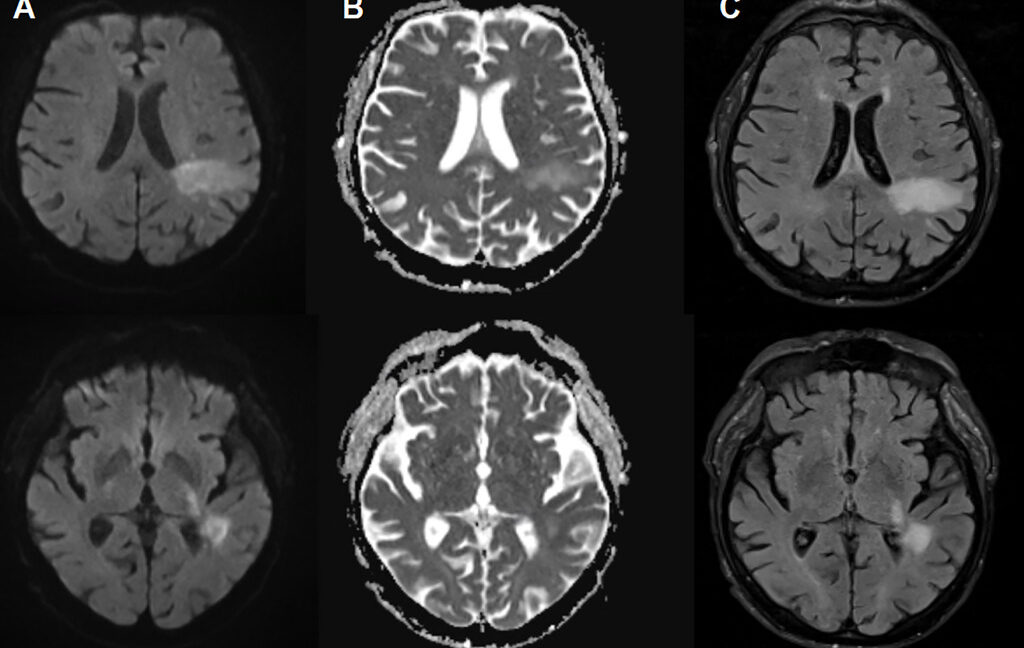

In PML, the new disease-causing virus or “PML-type” JC virus actively invades the brain, blowing up specific brain cells, including the cells that form the insulating myelin sheaths that protect nerve cells. This leads to extensive demyelination, which results in nerve cell dysfunction and death. On imaging, PML can show up as signature lesions in the brain. Those imaged lesions, paired with test findings of JC virus DNA in cerebrospinal fluid, are how PML is diagnosed. But for patients experiencing PML, the symptoms can mimic everything from a stroke to multiple sclerosis, causing problems like speech impairments, visual defects, motor dysfunction, and seizures.

Initially, they thought his neurologic problems were due to uremic encephalopathy, decreased brain function from toxin accumulation during kidney failure. They treated him with dialysis, but his word-finding difficulty only worsened. At that point, they did brain imaging, which revealed lesions seen in PML cases. Soon, testing on his cerebrospinal fluid confirmed the presence of the JC virus in his central nervous system. Two days later, the patient died.